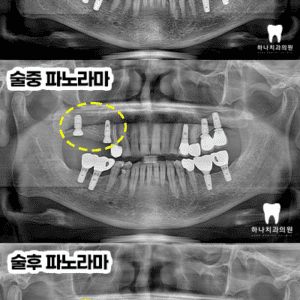

울산삼산동치과 치근 흡수된 어금니 발치 후 상악동 거상술 및 임플란트

울산삼산동치과 치근 흡수된 어금니 발치 후 상악동 거상술 및 임플란트   안녕하세요! 하나치과입니다~:) ​ 매복 사랑니는 잇몸이나 턱뼈 안에 묻혀 정상적으로 맹출 되지 못한 상태의 사랑니를 말합니다. ​ 역으로 눈에 보이지 않는 경우가 많아 불편함을 느끼지 못하고 지내는 경우도 많지만 구조적으로 음식물과 세균이 쉽게 쌓여 충치나 잇몸 염증이 반복되기 쉬운 더보기…